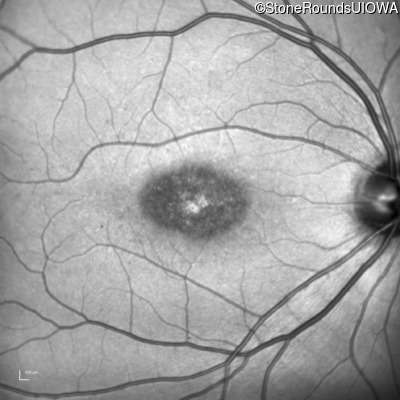

Infrared Fundus Photograph - Left - 20/125 sc

Exemplar